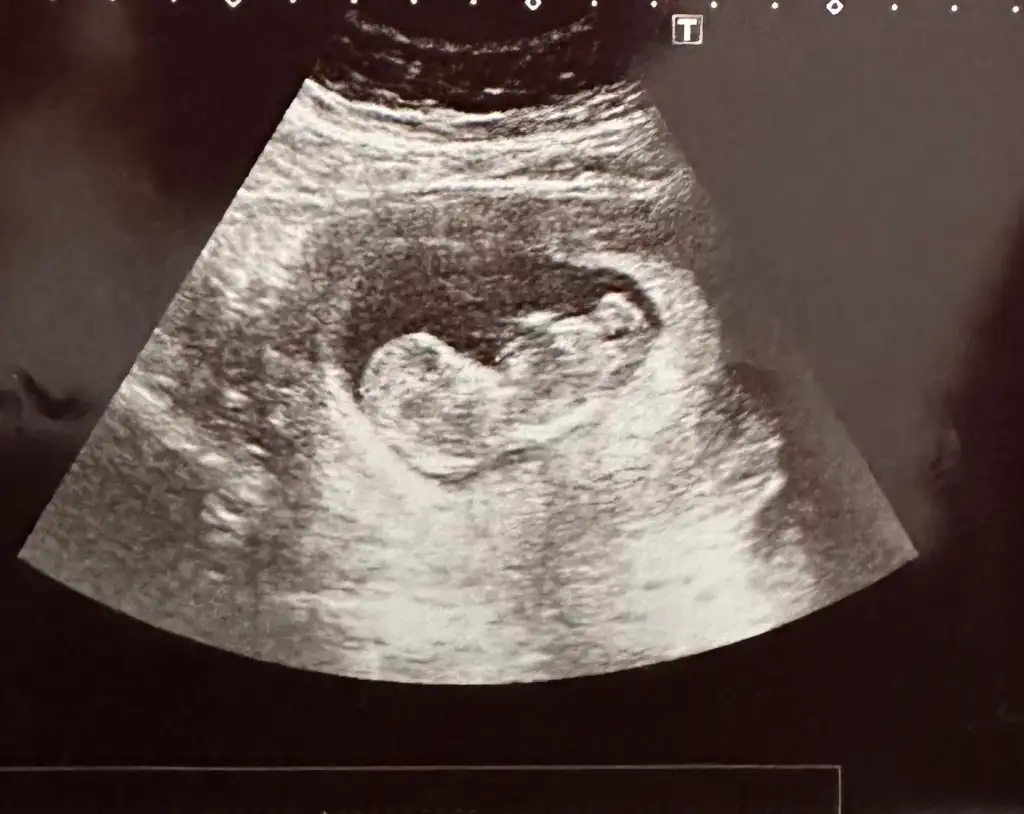

Ramzi teorisine göre tahmin yapalım

Merhaba 11+4 görüntüsü. Tahminlerinizi bekliyorum 🤩